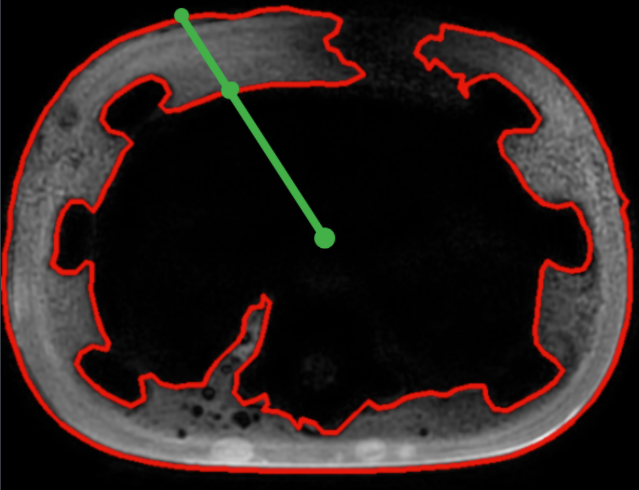

对当前轮廓(图中蓝色轮廓)和参考轮廓(图中红色轮廓)进行同步扫描。对于两个轮廓上相同θ的点的半径r,如果半径差大于设定的阈值,就认为是凹陷,如下图:

通过以上方式,我们能找到连续的凹陷点,两端就是凹陷的拐点,在两个拐点之间进行曲线拟合即可。

如上图所示:通过半径差能确定凹陷的边界origin_li,origin_ri.需要确保拟合曲线用得点在凹陷外,所以我先各自偏移十个点得到idx_li,idx_ri.之后再偏移十个点得到bound_li,bound_ri.用[bound_li:idx_li],[idx_ri:bound_ri]上的点进行B样条拟合.